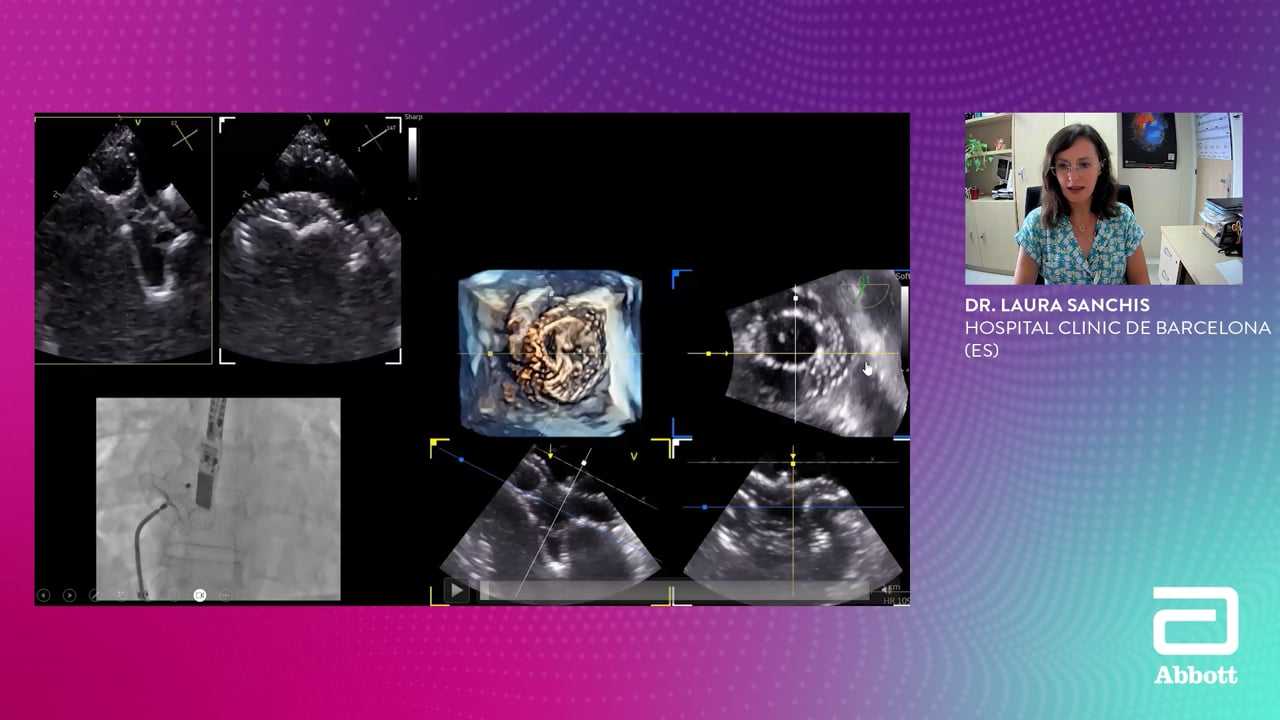

Atrial Septal Defects (ASD)

Learn from experts about echo screening, interventional guiding, and complication management for Atrial Septal Defect patients.